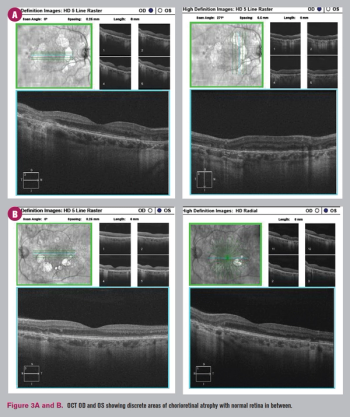

Case shows need to investigate further to provide patients with the correct treatment.